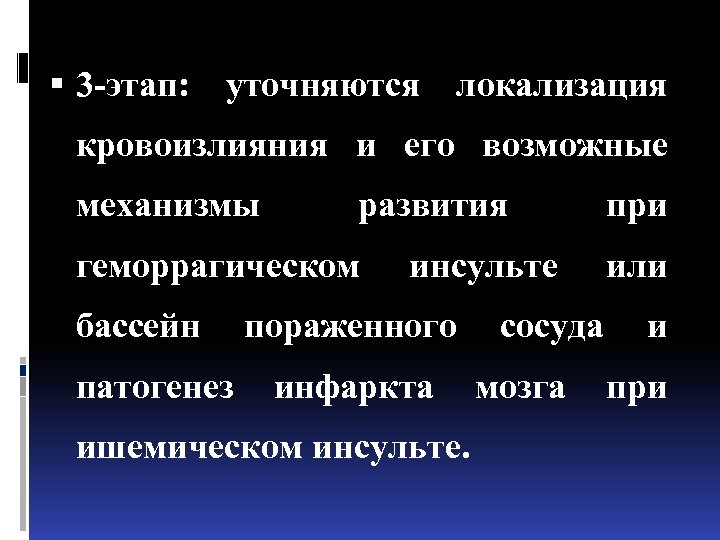

3 -этап: уточняются локализация кровоизлияния и его возможные механизмы развития геморрагическом инсульте при или бассейн пораженного сосуда и патогенез инфаркта мозга при ишемическом инсульте.

3 -этап: уточняются локализация кровоизлияния и его возможные механизмы развития геморрагическом инсульте при или бассейн пораженного сосуда и патогенез инфаркта мозга при ишемическом инсульте.